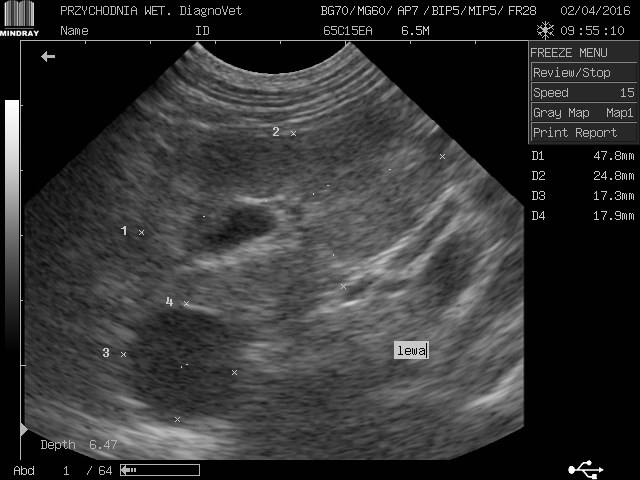

gracja1 Posted August 24, 2017 Posted August 24, 2017 Witam moja ukochana psinka gracja z wyników usg jest w bardzo kiepskim stanie nerki a praktycznie ich brak kwalifikują ja tylko do eutanazji jeżdżę od weta do weta i wszędzie żadnej pomocy.Gracja to piesek mieszany średniej wielkości trafiła do nas w ubiegłym roku ma zaledwie 2 lata.O chorych nerkach dowiedzieliśmy sie tydzień po przyjeździe jak do nas trafiła od początku objawy były ciągłe pragnienie wody i częstomocz decyzja tylko jedna jedziemy do weterynarza tam stwierdzono ze to zwykłe przeziębienie minęło parę dni brak poprawy u pieska powrót do weterynarza.Kazano zrobić badanie krwi moczu i wyszło kreatynina i mocznik podwyższony skierowano mnie na badanie usg tam potwierdziło chore nerki liczne cysty wokół diagnoza eutanazja natychmiastowa.Nie poddałam się minął rok z gracja od tamtej pory jest zemną bawi się biega kocha mnie nad życie lecz od paru dni dziwnie zaczęła się zachowywać jest osowiała mało zjada pije wodę wzięłam ja do weterynarza po diagnozie weterynarze są w szoku ze moja gracja żyję a na wieść o tym we dwoje zaczęli usg i to co zobaczyli to praktycznie brak nerek jedynie cysty do tej pory niewiadomo co tak naprawdę trzyma psa przy życiu i dziwią się ze on chodzi i biega w takim stanie a ja słyszę tylko w kółko pies do usypania zero szans zero leków absolutnie żadnej inicjatywy ze strony lekarza czy to normalnie dlatego jestem tutaj i opisuje swoja sytuacje a gracja leży przy mnie i nikt niepotrafi pomóc.Przesyłam skan usg krótko po przyjeździe gracji do mnie i pierwsze usg proszę o jakieś wskazówki do kogo jechać z kim porozmawiać bo siedzę i tony łez wylewam.Wyniki krwi z dnia 22.08.2017 Kreatynina 8.70mg/dl ,mocznik 300mg/dl 1 Quote